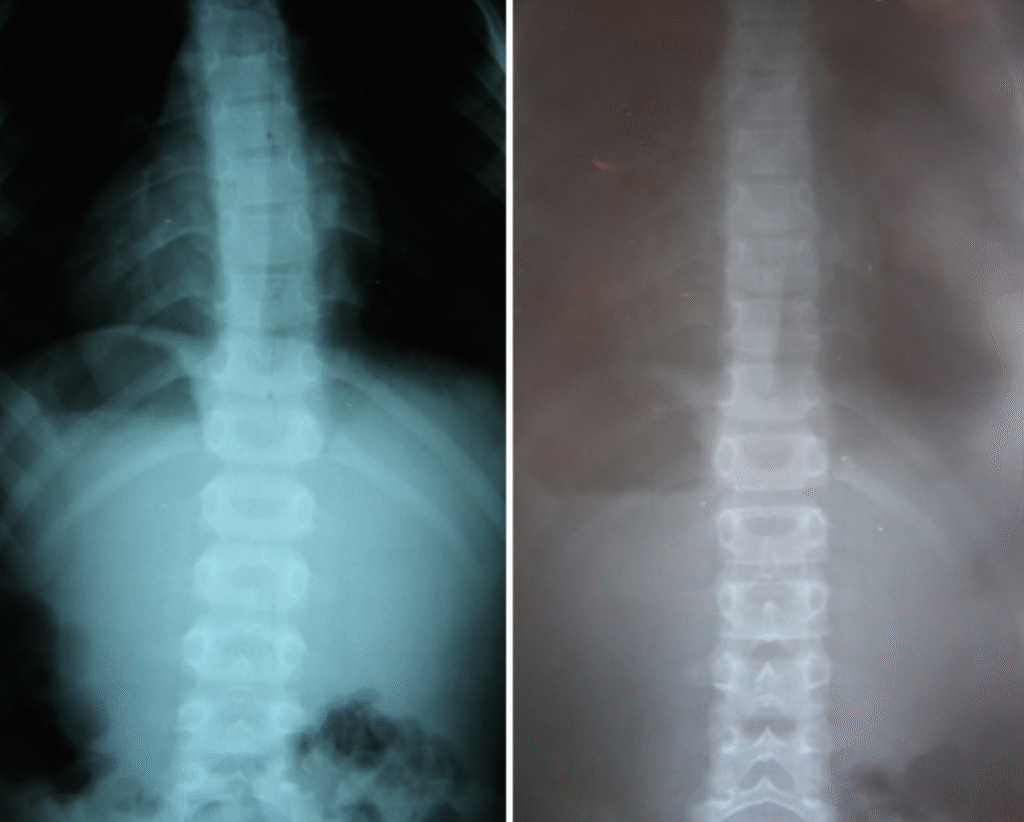

Maciej – 7 lat

Skolioza jednołukowa (statyczna) – zdj. z lewej. Korekcja uzyskana w trakcie jednej wizyty – zdj. z prawej